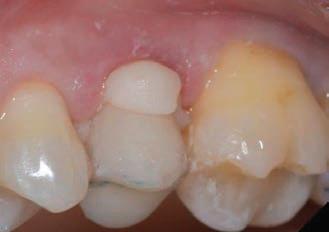

Figure 1: Initial situation. The patient reported generic pain in the second quadrant, where there was a restoration in temporary material on tooth number 25. Figure 2: Initial radiograph showing endodontic dressing that had been present for some months, but the treatment was never completed. Note the depth of the caries lesion and the proximity of the interdental bone ridge, which may represent an obstacle for prosthetic rehabilitation.

This element was not stimulated with the cold test and the radiographic image revealed an incomplete endodontic treatment (Figs. 1-2). The element seemed to present a suitable root length for a conservative restoration, but the apical position of the carious lesion and the proximity of the interdental bone ridge didn’t allow a correct rehabilitation with prosthetic crown, respecting the biological width.2